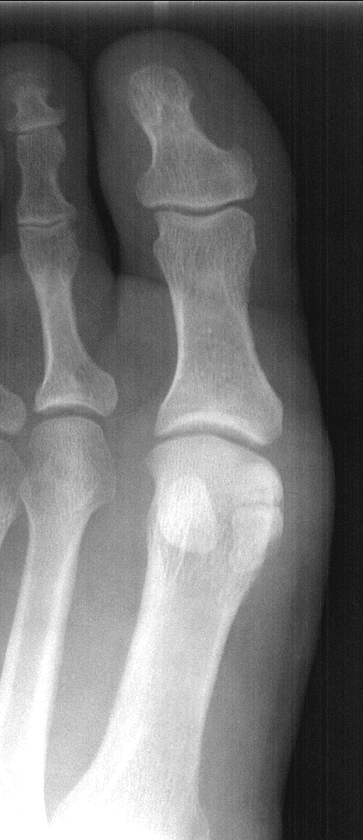

The big toe, or hallux, has two phalanges and two joints (interphalangeal joints); it also has two tiny, round, sesamoid bones that enable it to move up and down. On an x-ray of the foot, they appear as a pair of distinctive oval dots near the first metatarsal head (front end of the first long bone of the forefoot). The other four toes each have three phalanges, two joints, and no sesamoid bones.

The sesamoid bones closest to the inner side of the foot are called medial sesamoid bones; the ones closest to the outside of the foot are called lateral sesamoid bones.